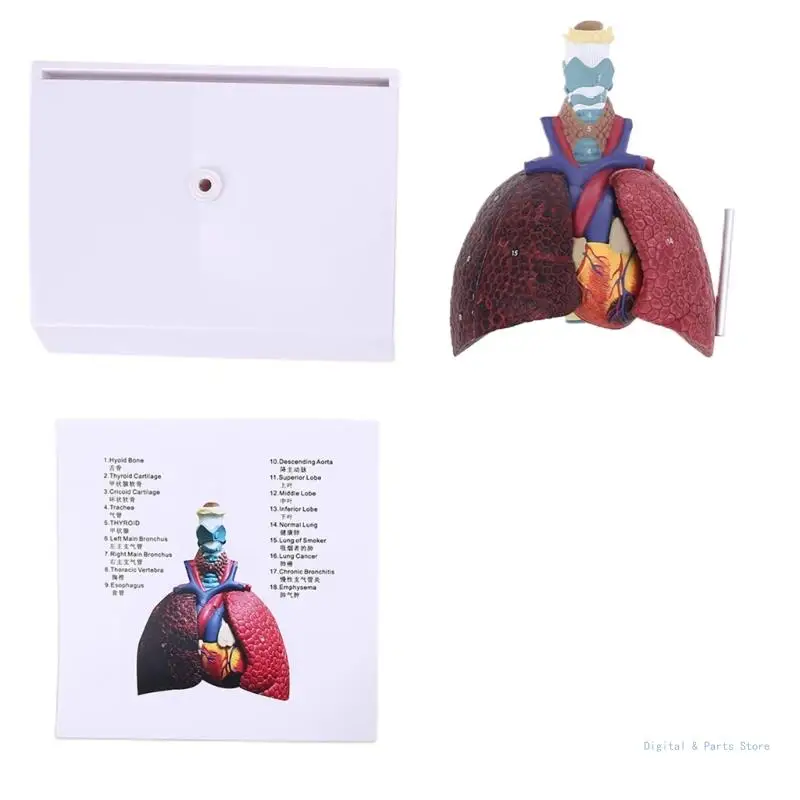

M17F Life Size Human Lung Model Anatomical Respiratory System Anatomy Teaching Tool

Human Larynx/Heart/Lung Anatomical Model Medical Model Pulmonary Anatomy Model Respiratory System Model Teaching Supplies

Lung Respiratory Anatomy Model Teaching System Human Display model School Lungs Anatomical Heart Educational Nasal Toy

Lung Respiratory Anatomy Model Teaching System Human Display model School Lungs Anatomical Heart Educational Nasal Toy

Lung Respiratory Anatomy Model Teaching System Human Display model School Lungs Anatomical Heart Educational Nasal Toy

Lung Respiratory Anatomy Model Teaching System Human Display model School Lungs Anatomical Heart Educational Nasal Toy

PVC Respiratory System Model Lifelike Teaching Aid for Medical Schools Anatomy Education Practical Human Lung Display Tool

Diseased Human Lung Structure Respiratory System Model for Anatomical Study Display Teach Anatomy Medical Supply and Equipment